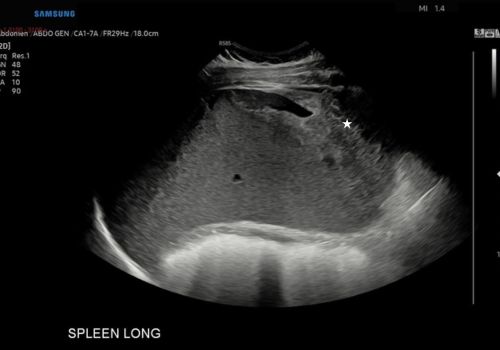

A heterogenous area with a small area of central fluid left subphrenic space surrounding/indistinct from the superior spleen was identified with no colour doppler flow.